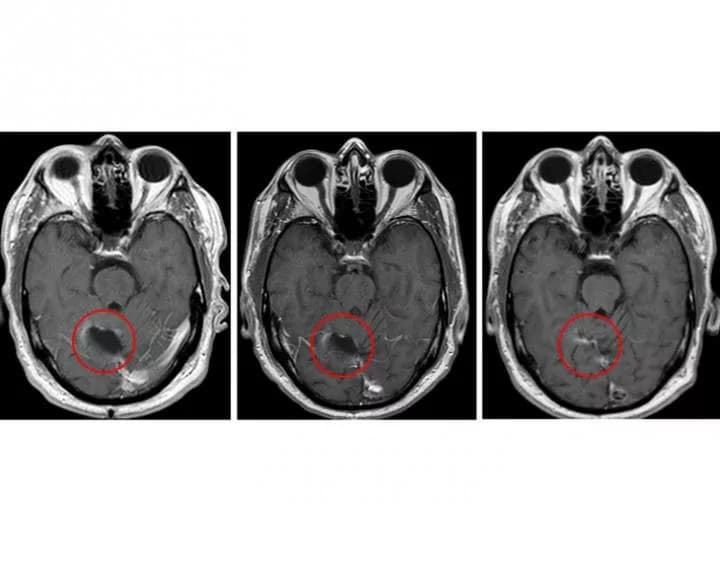

Batich said the approach significantly slowed the progression of patients' tumors. Typically, glioblastoma tumors begin to regrow after standard treatment at a median of eight months, but for study participants, recurrence occurred at a median of 25 months.